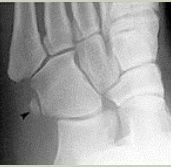

| What disease is this? What does the arrow indicate? | Rheumatoid arthritis. Arrow = Bone erosion secondary to inflammation of retrocalcaneal bursa. |